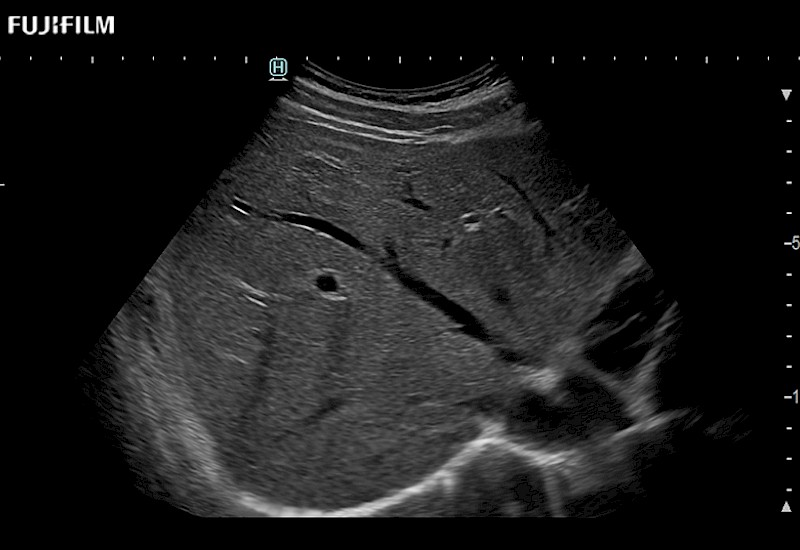

for use during open and laparoscopic procedures: Tumor localization & staging, Ablation, Resection, Biopsy, Transplant, Abdominal exploration, Robotic surgery

Learn moreFujifilm Healthcare continues to listen to the experts, our neurosurgeons, by developing an ultrasound system specifically designed for the Operating Room.

Guidance is the fundamental purpose for all of our surgical ultrasound technology. Fujifilm Healthcare is committed to designing tools that help neurosurgeons navigate inside the human body and provide the necessary information to immediately make critical surgical decisions.

With the ARIETTA Precision the next level of surgical ultrasound is here.